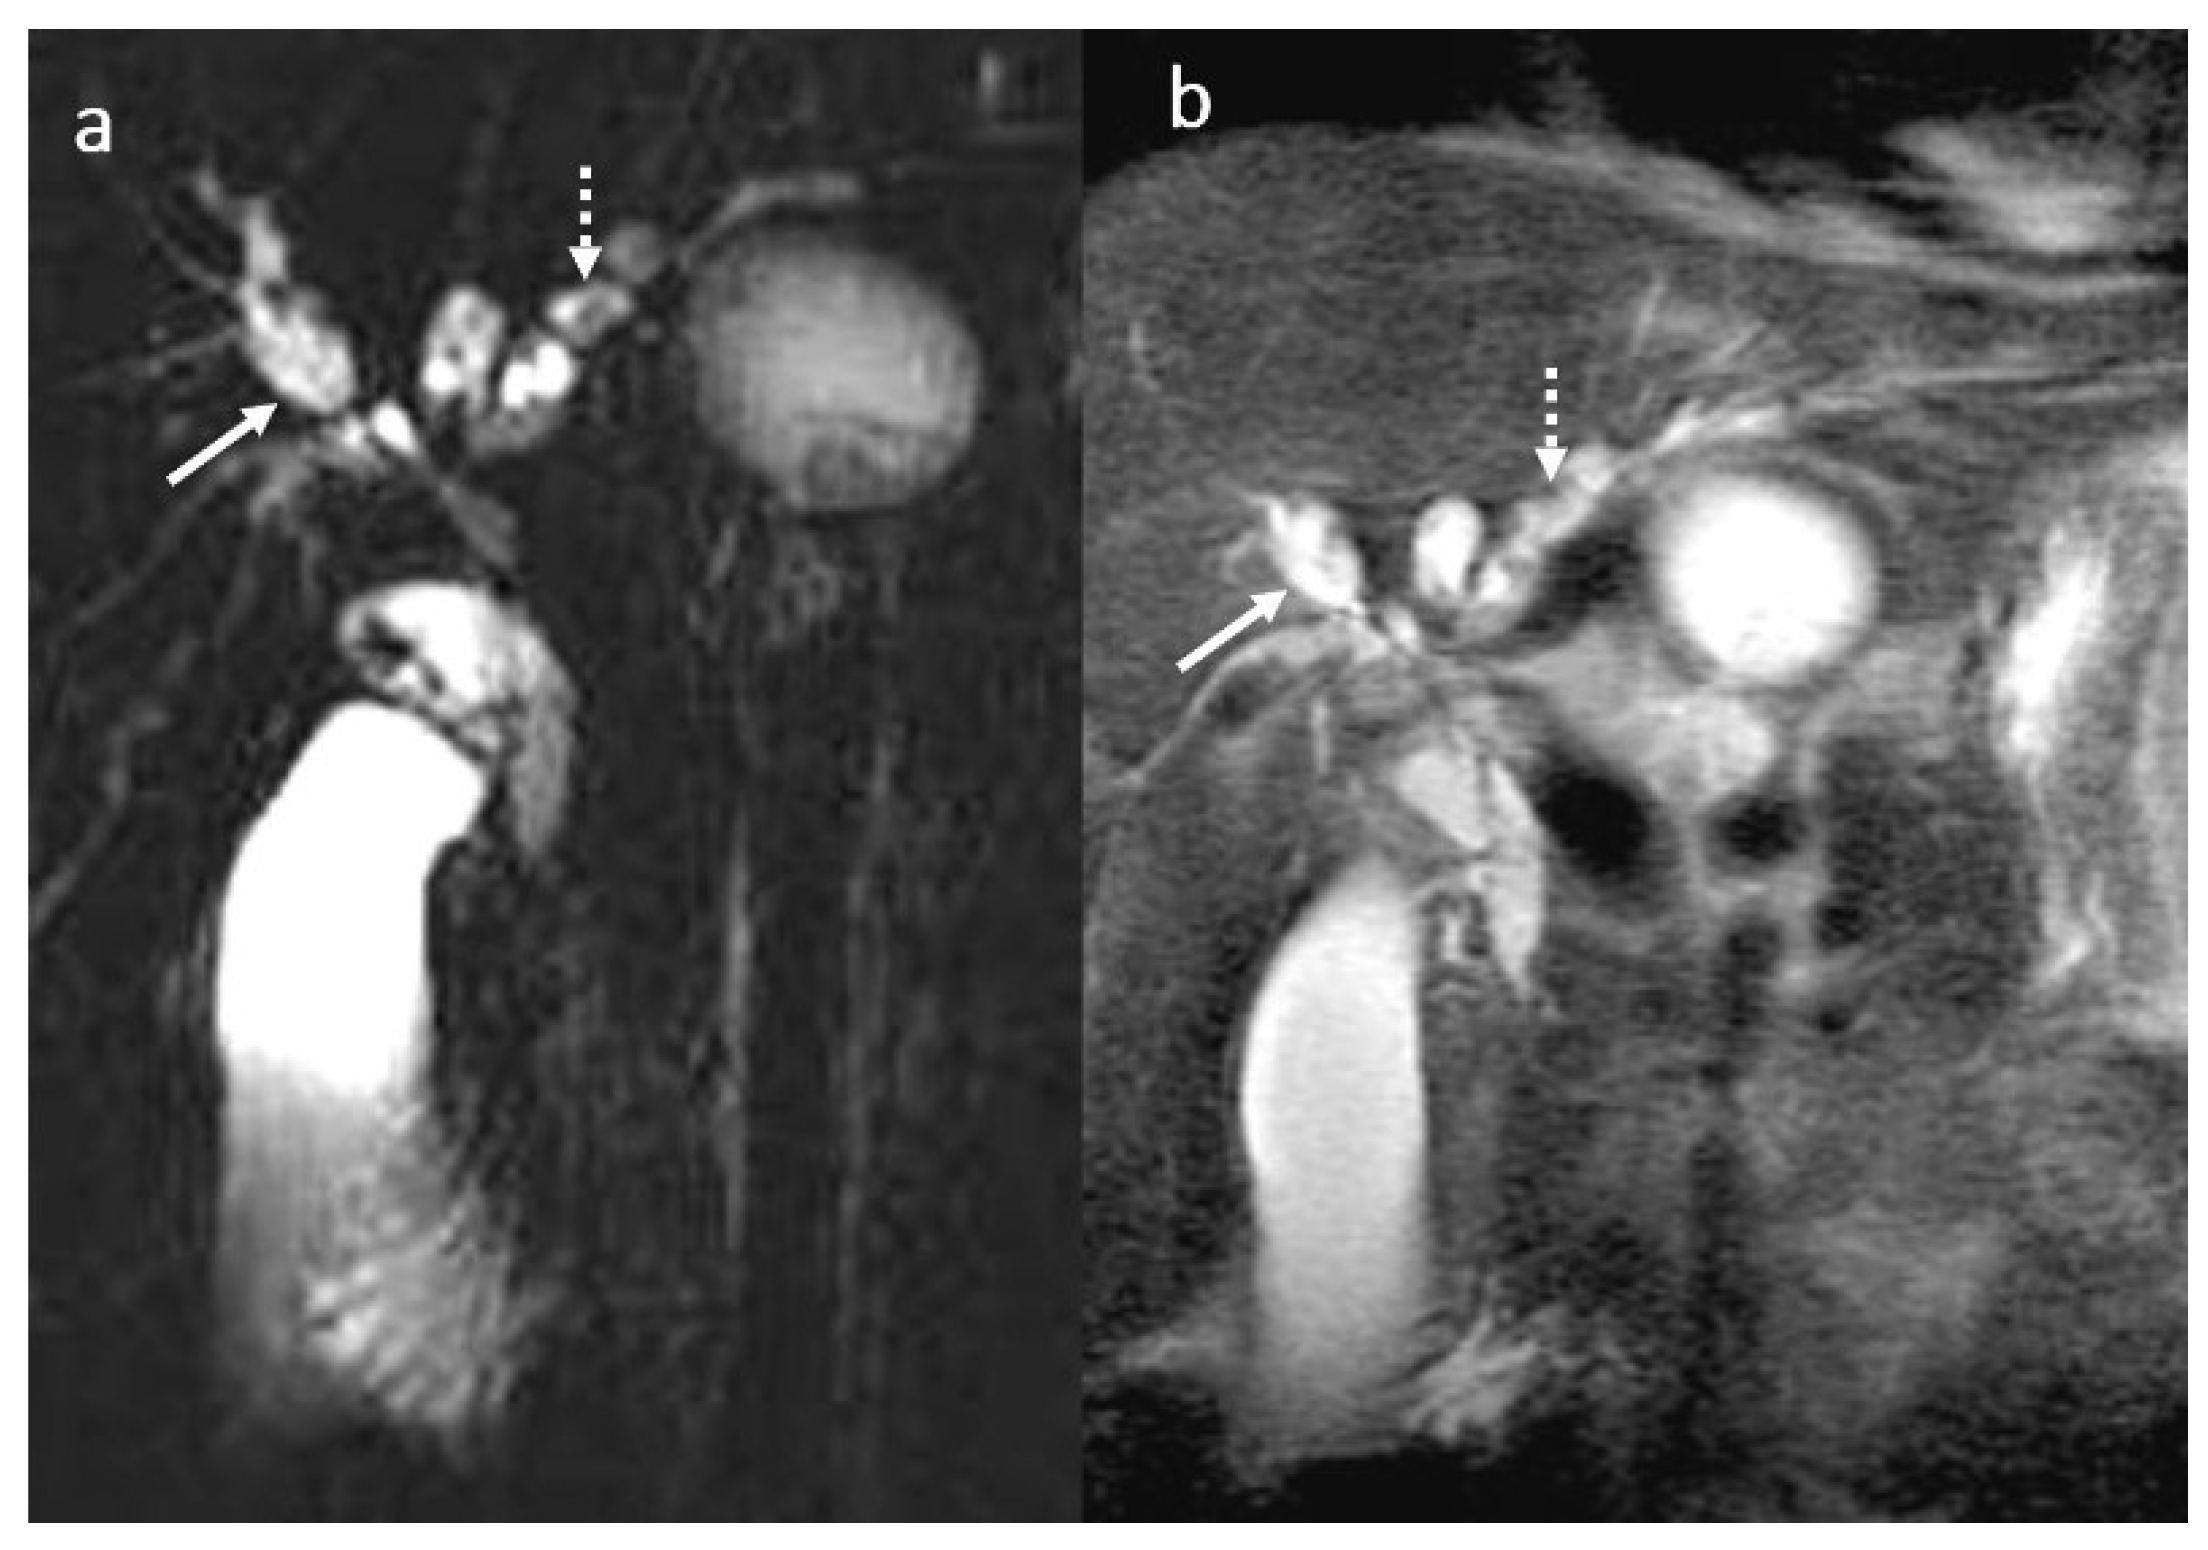

3.6. Secondary Cholangitis